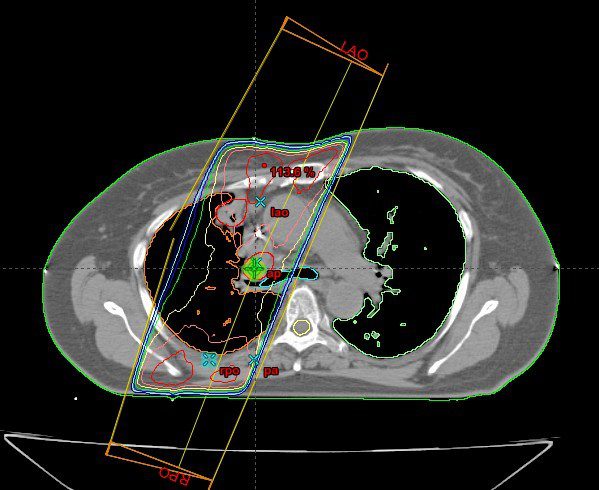

Radiation Therapy For Non-Small Cell Lung Cancer | Caring Ambassadors

Radiation Therapy for Non-Small Cell Lung Cancer | Caring Ambassadors lungcancercap.org

radiation therapy lung cancer cell non intensity modulated